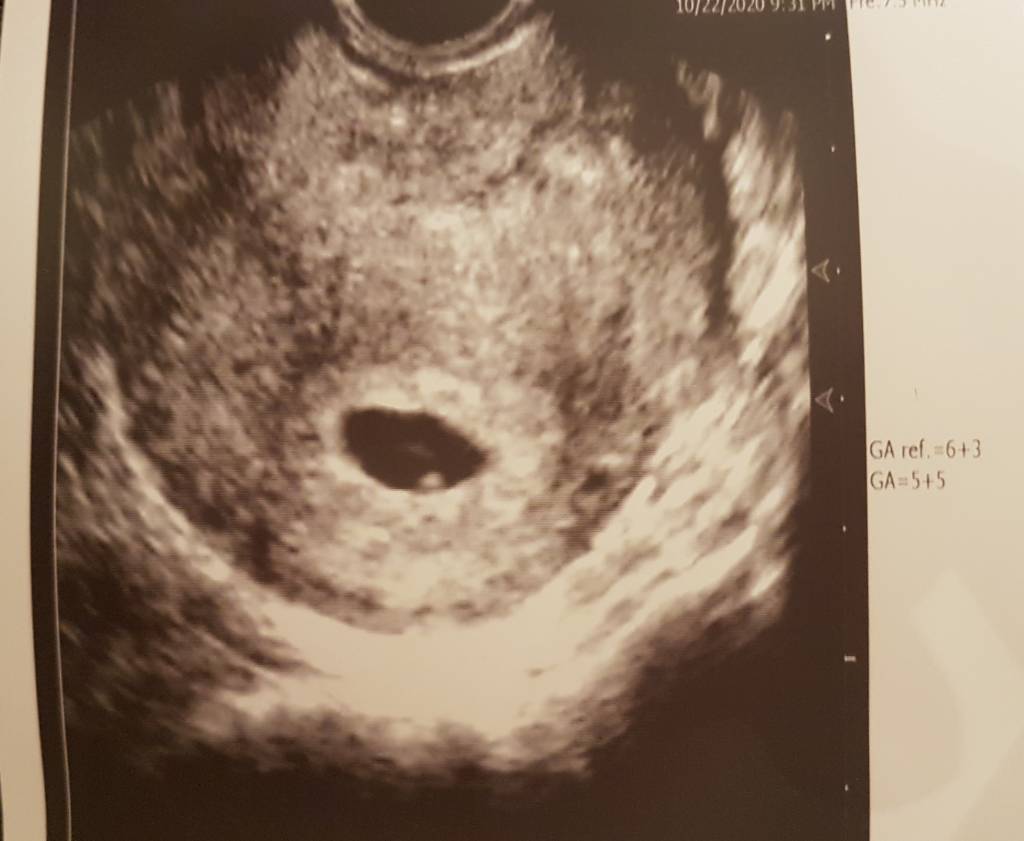

Witam. Jestem po wizycie. Wszystko jest ok. Pęcherzyk we właściwym miejscu, jeden

4mm. Ciąża z usg jest młodsza niż z om (z OM 6t3d z usg 5t5d) W sumie to nie wiem kiedy miałam owulacje... Karta ciąży założona, następna wizyta 18.11